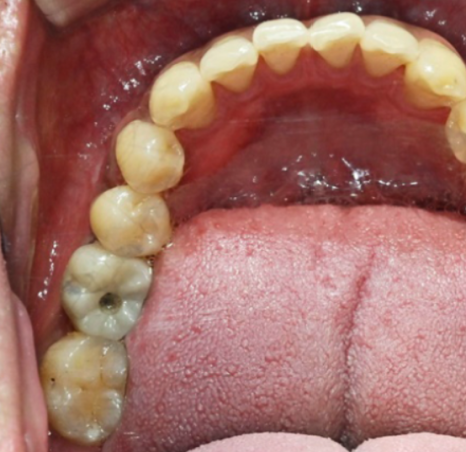

[스마일디 임플란트 사례 중 일부]

치료기간: 23.12.25일-24.06.28 (약 6개월)

진행한 치료: 발치 후 염증치료, 골이식과 임플란트2개 식립후 브릿지

치료기간: 24.11.03일-24.12.03(약 1개월)

진행한 치료: 발치 후 임플란트

*치료 전후 사진은 환자의 동의하에 게재하였으며, 동일한 환경과 조건에서 촬영된 전후 사진입니다.